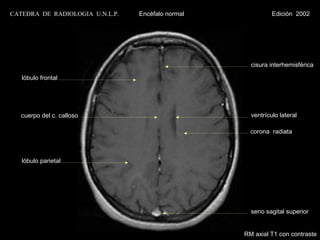

CATEDRA DE RADIOLOGIA U.N.L.P.   Encéfalo normal             Edición 2002

cisura interhemisférica

lóbulo frontal

cuerpo del c. calloso                             ventrículo lateral

corona radiata

lóbulo parietal

seno sagital superior

RM axial T1 con contraste